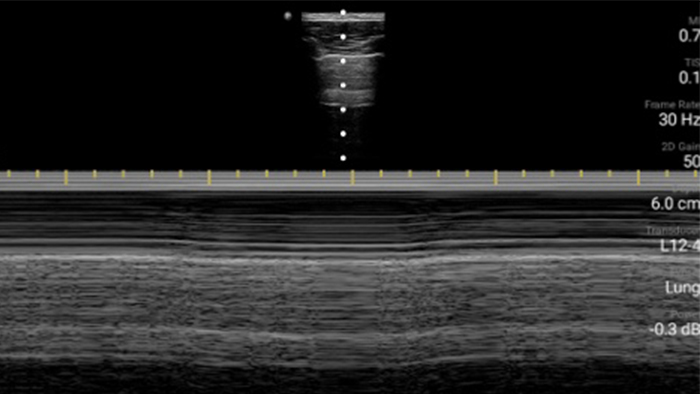

Keep an eye on COVID pneumonia

Lumify can help give results similar to a chest CT when evaluating pneumonia and adult respiratory distress syndrome.